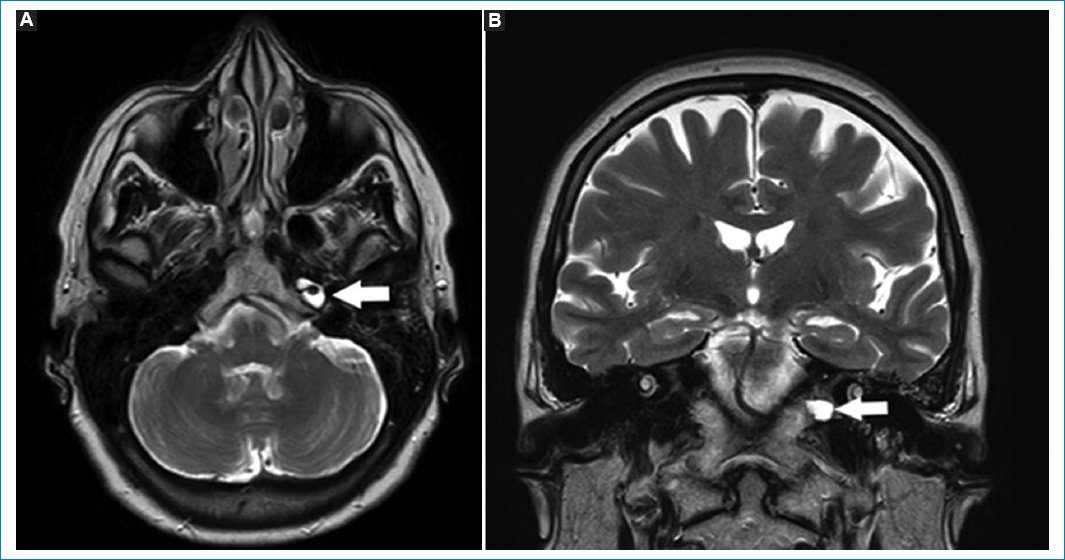

Figura 4. Imágenes potenciadas en T2. Corte axial (A) y coronal (B). Las flechas indican la presencia de meningocele cavernoso izquierdo. Este es valorado como un aumento del volumen del seno cavernoso afectado.

La efusión del ápex es acúmulo del líquido estéril, sin asociarse a síntomas clínicos. Las cavidades mastoideas presentan continuidad con el ápex petroso, por lo que pueden drenar su contenido en un ápex neumatizado29. Se objetiva hipointenso en T1 e hiperintenso en FLAIR y T2, sin realzar con gadolinio (Fig. 9)29.

Figura 9. Imágenes potenciadas en T2. Cortes: axial (A) y coronal (B). Se observa (flechas) colección en el ápex izquierdo. Esta es hiperintensa en T2, resaltando en comparación del ápex neumatizado contralateral.